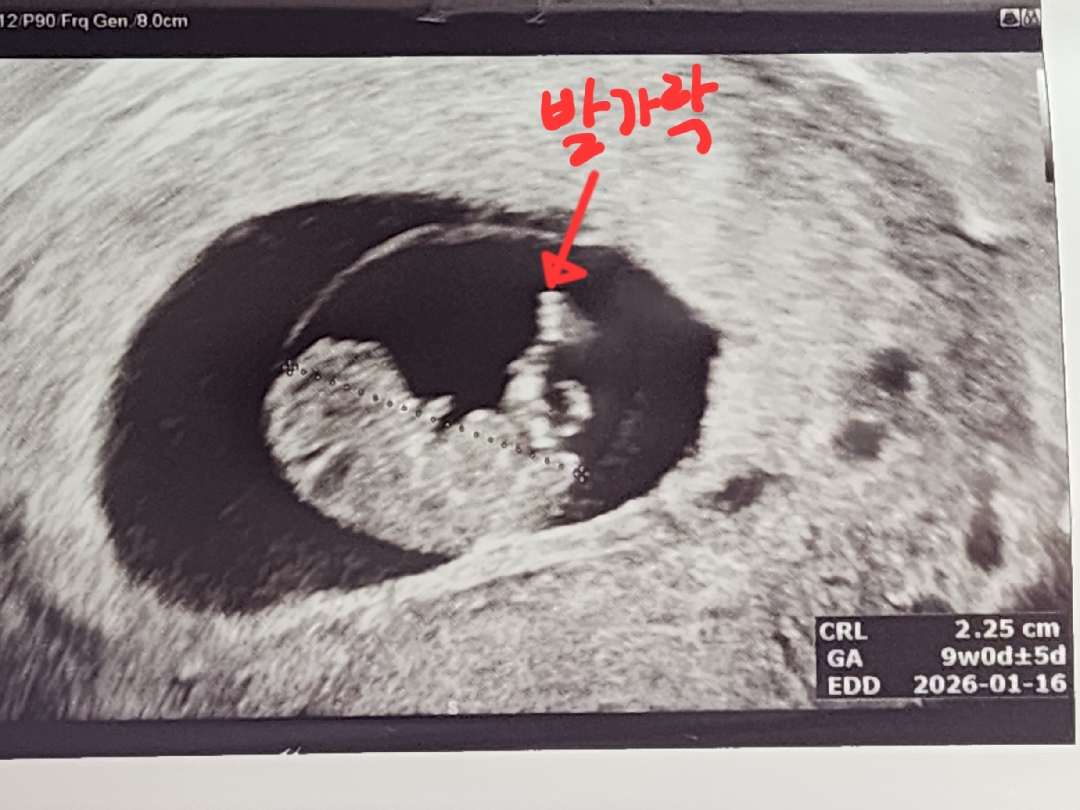

9주1일 손가락 발가락 보고왔어요😆

꼬물꼬물 움직이는 모습도 보이고.. 움직이는걸 보니까 진짜 내 뱃속에 사람이 살고있구나 실감이 나네요😭 전 귀여운 젤리곰은 못봤지만... 사람을 보고왔습니다ㅋㅋㅋㅋ 다들 귀여운 아가 쑥쑥 크는모습보길 바라요!